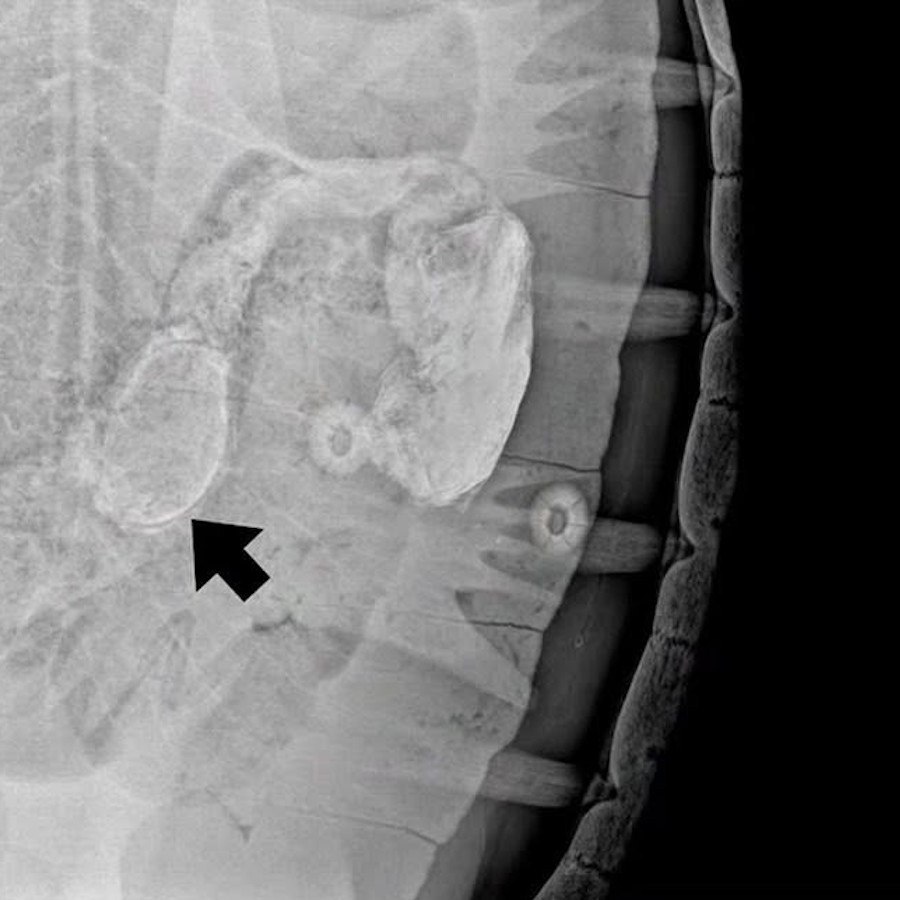

Пластиковый браслет был «скормлен» черепахе некими туристами 21 ноября на Симиланах. Животное было найдено, поймано и передано сотрудникам Пхукетского центра морской биологии (PMBC). Рентгенография подтвердила нахождение предмета в пищеварительной системе черепахи. Только 18 декабря, почти месяц спустя, животному удалось избавиться от браслета.